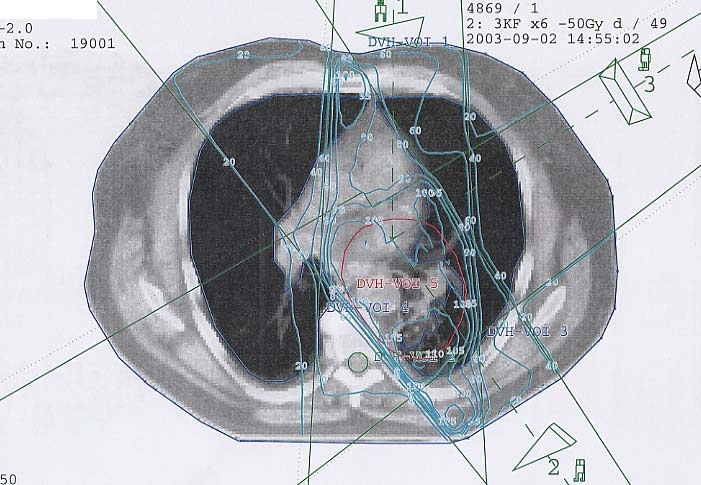

Bronchialkarzinom: Bestrahlungsplan